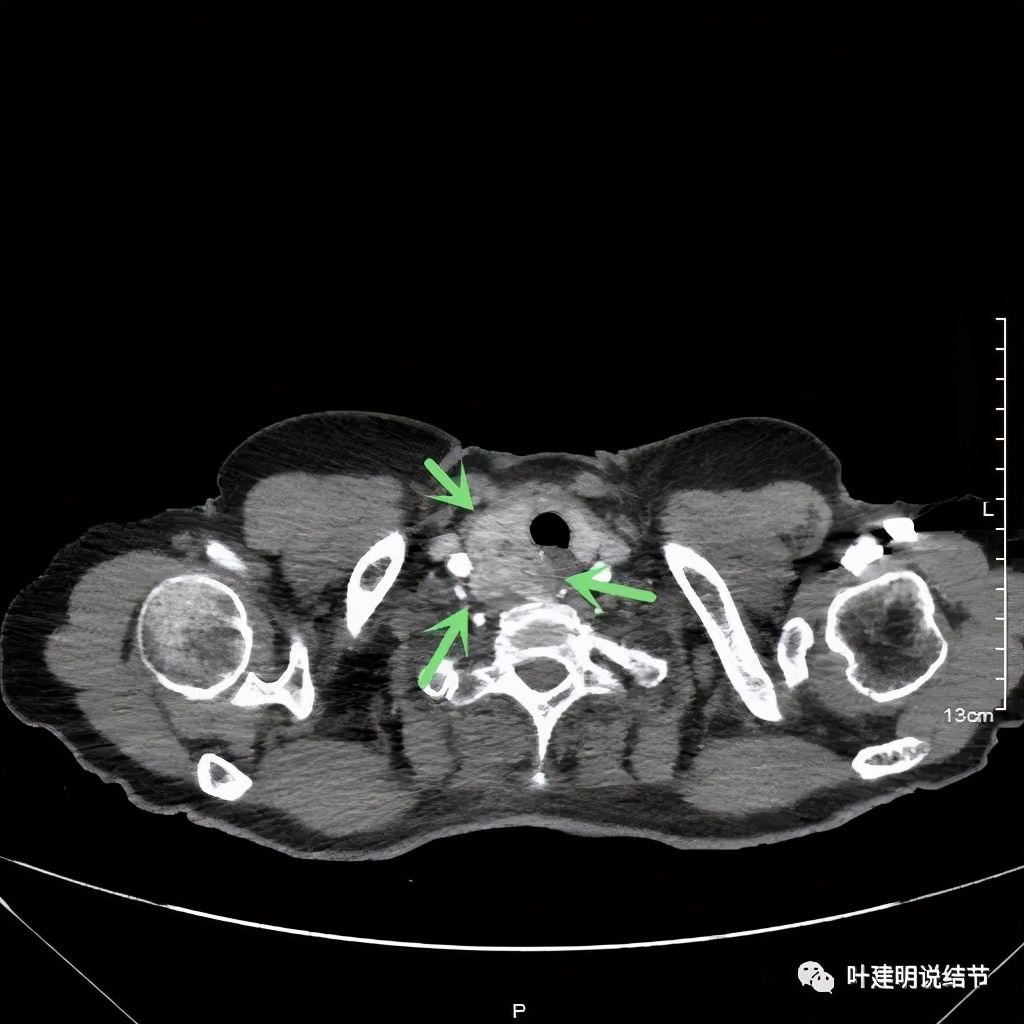

金华地区的某A,今年已经76岁了,近段时间觉得胸闷不适,还有刺激性咳嗽,总是不会好,到当地医院查了胸部CT,发现是纵隔肿瘤。当地医生建议她到金华市中心医院做下气管镜下穿刺活检,以明确肿瘤性质。因为认识我们医院的某外科主任,所以又建议她来找我,结果我一看她从当地带来的片子,是纵隔内巨大的占位,与气管关系密切,位于气管右侧、食管右前侧、上腔静脉左侧、无名静脉后侧,被诸多结构包绕着,而且肿瘤密度不均,靠气管与无名静脉侧间隙不清,首先考虑纵隔内恶性或交界性肿瘤,由于年纪这么大,手术风险较高,若与气管有侵犯,则手术达不到根治,我也觉得应该先行经气管镜下的穿刺活检,明确病理后再考虑怎么办。所以让某A住到呼吸内科去,打算行气管镜下纵隔肿瘤穿刺活检。因当地的片子扫到胸顶部为止,没有做增强,我们先取本院增强片子上达胸顶,下达肿瘤下缘的范围来看看肿瘤的样子:

我们由胸顶再往颈部一层一层看,结果真的肿瘤是与右侧甲状腺相连的!那么应该可能是甲状腺来源的纵隔肿瘤(胸内甲状腺肿瘤)。这样的话,其他的边缘界限清楚,这种密度以结节性甲状腺肿可能性大,不太像甲状腺恶性肿瘤。那么与气管间估计也是紧密靠着而已,不会是侵犯的。所以我们商量后就不穿刺,打算直接手术切除。术前做了冠脉CT,也有点问题,好在冠脉狭窄程度不重: